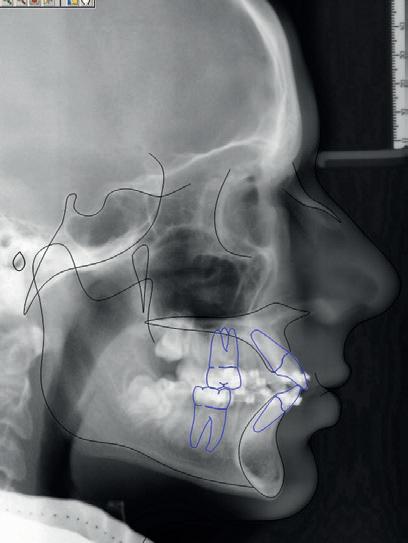

RECONFIGURAREA suportului osos implantar. În cazul prezentat, după ani de terapie ortodontică incorect executată, dezvoltarea dentară a pacientului a complicat obținerea unui zâmbet estetic. S-a reanalizat și s-a optat pentru abordare interdisciplinară care cuprinde chirurgia parodontală, un al doilea tratament

ortodontic și protetica pentru a oferi îngrijirea comprehensivă.